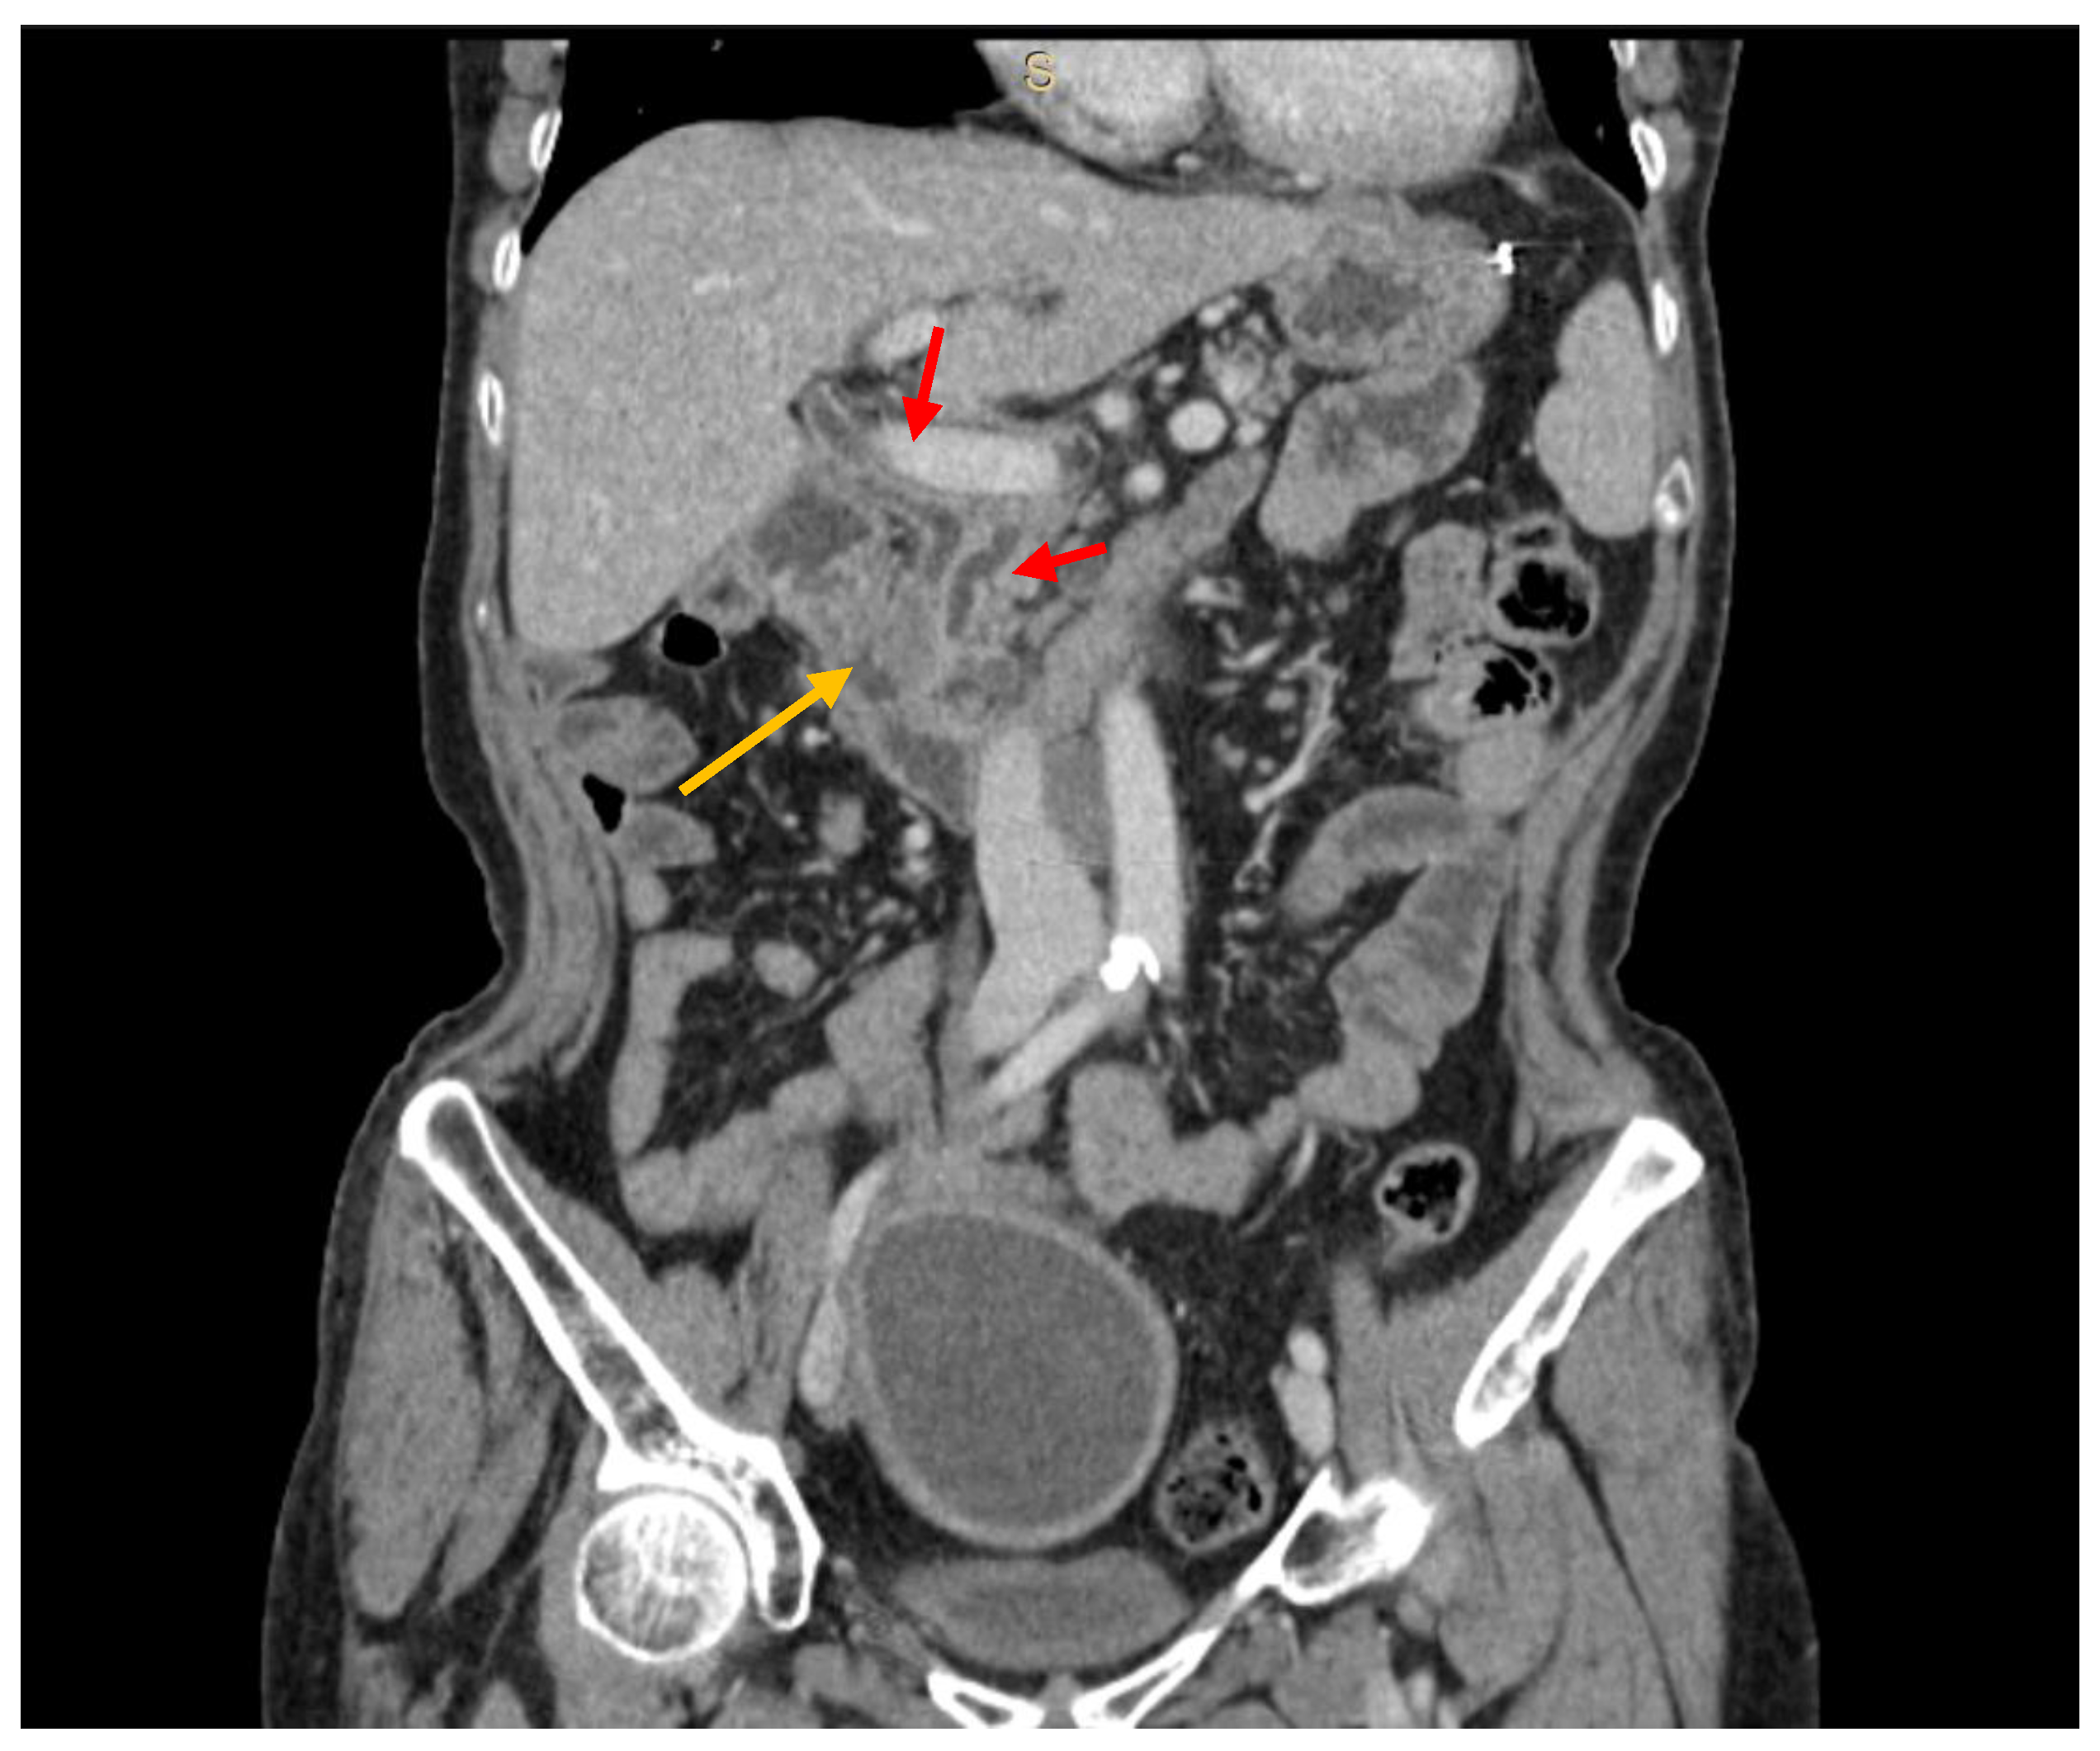

Figure 2.

CT scan showing a hypovascular lesion (yellow arrow) of the pancreatic head, causing both bile duct and panceatic duct dilation (red arrows) (PM from colon cancer).